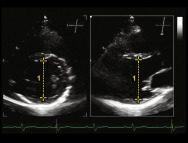

| 3.2a. Cửa sổ siêu âm cạnh ức Ghi hình 2 bình diện | ![]() | Hình ảnh Biplane có thể giúp đặt chùm siêu âm vuông góc với cấu trúc để đo chính xác các kích thước trên hình ảnh 2D 1. LVDs = 47.0 mm | ||||

| 3.2b. Cửa sổ siêu âm cạnh ức Ghi hình 2 bình diện từ trục chính giữa thất trái | ![]() | Hình ảnh Biplane này cho thấy kết quả của việc đo trên hình ảnh lệch trục. 1. LVDs giảm từ 47.0 mm (hình 3.2a) xuống còn 44.0 mm. | ||||